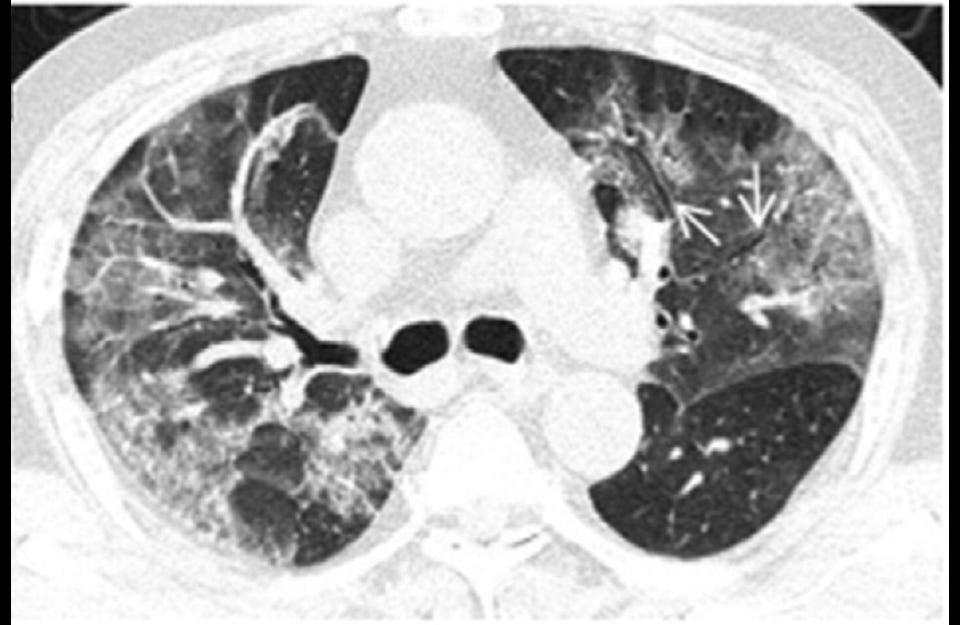

Patients with severe cases typically develop fluid in their lungs, similar to those seen in standard pneumonia cases. That fluid can be detected on a CT scan, where it shows up in the form of white patches that doctors call "ground glass."

But coronavirus scans tend to have white patches that radiologists refer to as "ground glass opacity."

But the patches are significant, he added, when they extend to the edges of the patient's lungs.

An analysis of nearly 140 coronavirus scans suggests that patches of ground glass on both lungs are a hallmark of the virus ?

Many coronavirus patients tend to worsen quickly. Their ground-glass patches become more pronounced after a few days.